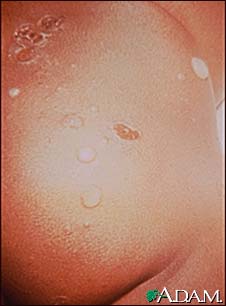

Impetigo, bullous on the buttocks

Impetigo is a superficial skin infection caused by either streptococci or staphylococci. Here it is on the buttocks, but it is seen more frequently in children on the face, upper chest, and arms. (Image courtesy of the Centers for Disease Control and Prevention.)